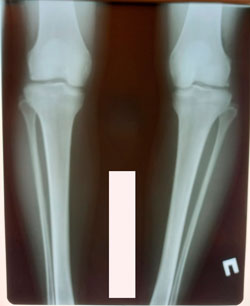

Исходник - 28 лет.

Дата операции - 08.12.2020

Диагноз; Варусная деформация голеней + Ротация с обеих сторон